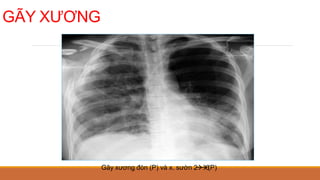

GÃY XƯƠNG

Gãy xương đòn (P) và x. sườn 2



6

(P)